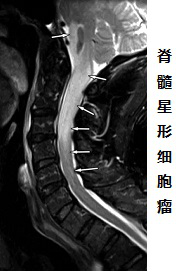

脊髓胶质瘤,顾名思义,即为脊髓内肿瘤,是一种恶性肿瘤,通常生于脊髓内。脊髓胶质瘤与周围生理组织往往没有明显边界,表现为生长浸润性,导致脊髓呈现增粗、肿胀。

脊髓胶质瘤是较常见的脊髓肿瘤,占脊髓髓内肿瘤的80%以上,其年发病率约为0.22人每10万人[1]。脊髓胶质瘤可以是原发性的,多数是转移性的。原发性脊髓肿瘤很少见,通常是良性的。病理上脊髓胶质瘤主要表现为室管膜瘤或星形细胞瘤。室管膜瘤常见于成人,星型细胞瘤是儿童发病率较高的髓内肿瘤。其他还可见血管母细胞瘤、脂肪瘤等。根据肿瘤的解剖位置(肿瘤与脊膜的关系),脊髓胶质瘤分为硬膜内肿瘤和硬膜外肿瘤。生长在脊髓内的的肿瘤称为髓内肿瘤。在椎管内而在脊髓组织外发生的肿瘤称为硬膜内-髓外肿瘤。硬膜外肿瘤占脊髓肿瘤的多数。

脊髓髓内肿瘤(IMSCT)的组织病理学表现主要根据磁共振成像(MRI)表现及特征加以确定。